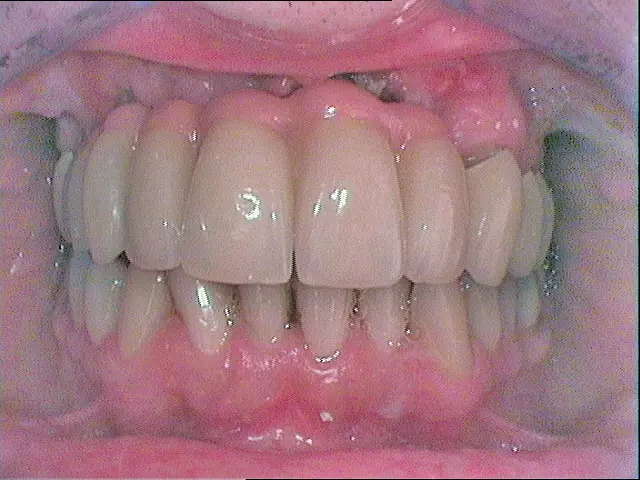

Nach Freilegung der Implantate regio 026,027 im Februar 2020, bei der auch die Implantation regio 037 (T3, Zimmer Biomet Dental, 4,0 mm x 13,0 mm) vorgenommen wurde (Abb. 32 OPG nach Freilegung), erfolgte im März nach Abformung mit offenem Löffel (open tray technique) und Gesichtsbogenregistrat die prothetische Versorgung mittels CAD/CAM gefräster Abutments (Dentaltechnik Hessel und Lutgen, Trier) und transversal verschraubter, verblockter VMK-Kronen (Abb. 33-36). Die Freilegung und Versorgung des Implantates 037 ist zusammen mit der Entfernung des Zahnes 38 für Juli 2020 geplant.